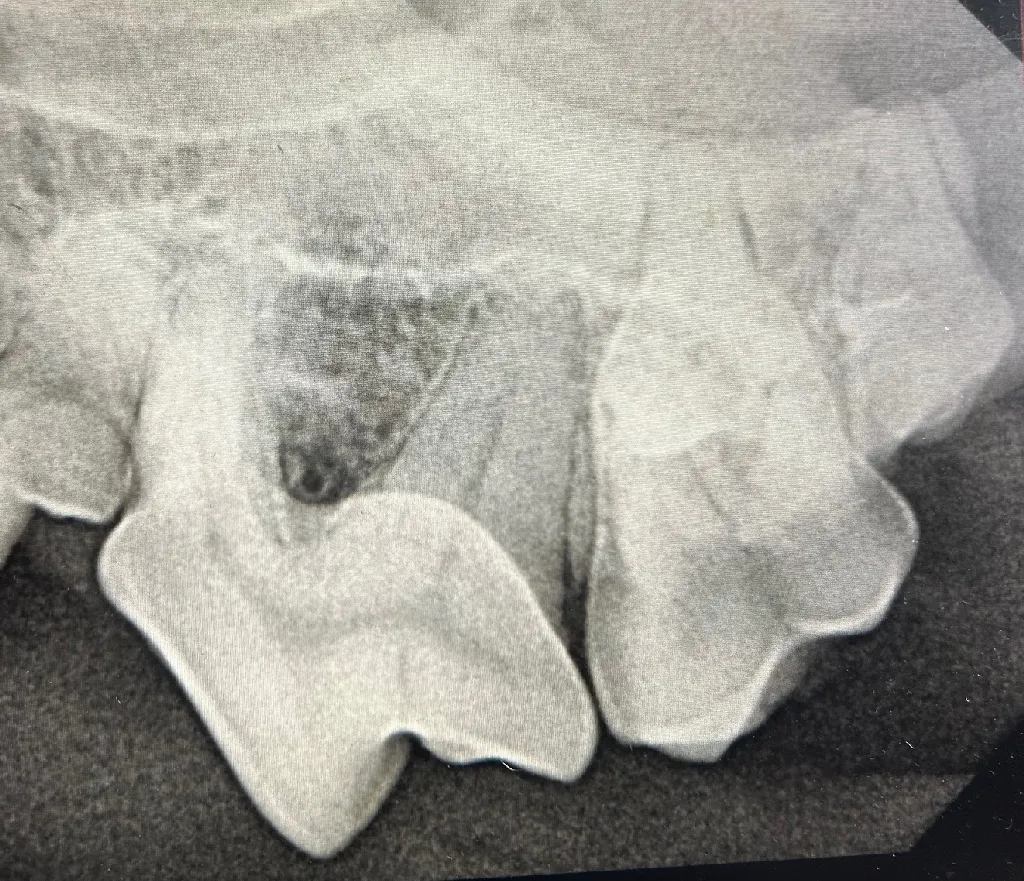

At Meadowmont Animal Hospital, we employ advanced digital radiology technology to swiftly and accurately diagnose your pet’s medical conditions. Digital radiology allows us to obtain detailed, high-resolution images of your pet’s internal structures quickly, minimizing stress and discomfort. These services are available for pets, ensuring comprehensive care for all species.

- Enhanced ability to diagnose fractures, internal abnormalities, and dental conditions